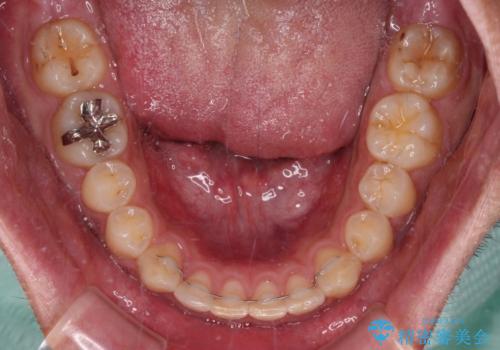

深い咬み合わせと隙間の空いた歯列をワイヤー矯正で改善

- 前歯の隙間と深い咬み合わせを改善したいとのことで来院された患者様です。

マウスピース矯正の自己管理が面倒とのことで、ワイヤー矯正により治療を行うこととしました。

奥歯の咬み合わせは理想的な状態であったため、ワイヤー矯正でもインビザラインでも比較的容易に対応可能でした。